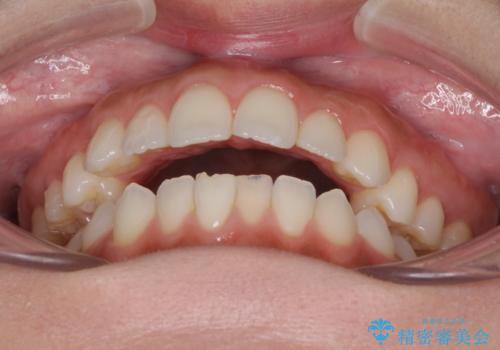

前歯のオープンバイトを治したい インビザラインでの矯正治療

- 前歯の上下スペースによる話しにくさと顎への負担を気にして来院された患者様です。

インビザラインにより上顎の大臼歯を圧下し、上下の前歯の隙間を閉じていくこととしました。

上顎の奥歯を圧下させることで、上下前歯を接触させるように計画しました。

前歯が急に接触するようになり、慣れるまで時間がかかりましたが、前歯でものが咬めるようにもなり、患者様には大変満足していただきました。